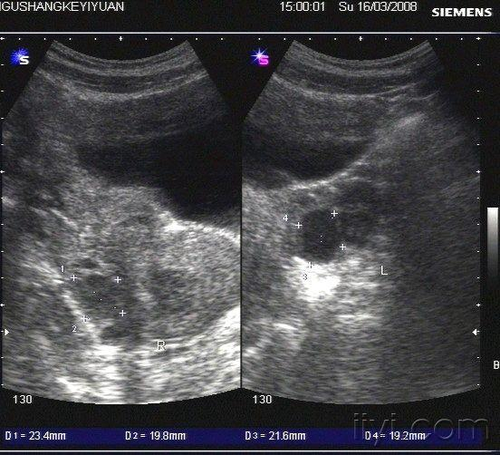

巧囊是由于女性的子宫内膜移位到卵巢导致的一种炎症。巧囊的治疗只能依靠手术和绝经来治疗。巧囊手术之后虽然短期治疗好,但是以后还是有可能会复发的。那么巧囊复发率会有多高呢?